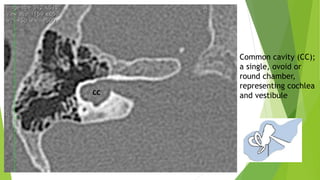

4- Common Cavity

A CC is defined as a single, ovoid or round chamber, representing

cochlea and vestibule. Theoretically, this structure has cochlear and

vestibular neural structures.

The IAC usually enters the cavity at its center. Cases with vestibular

Common cavity (CC);

a single, ovoid or

round chamber,

representing cochlea

and vestibule